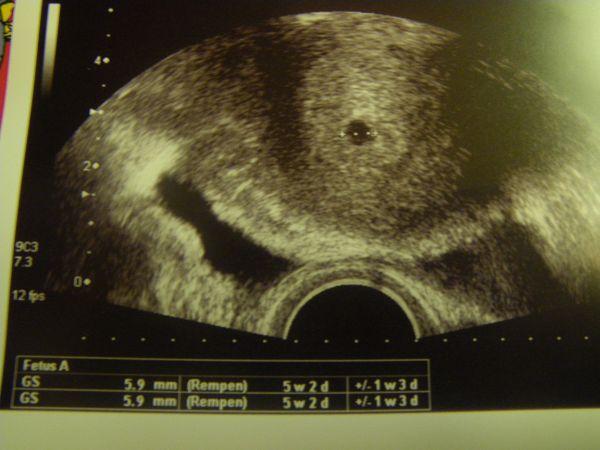

also meine war gestern 5,9 mm und es stand dann da 5+2....

Bild zu wie gross waren denn eure fruchthöhlen so in der 6 woche? - Forum für Juli - Mamis